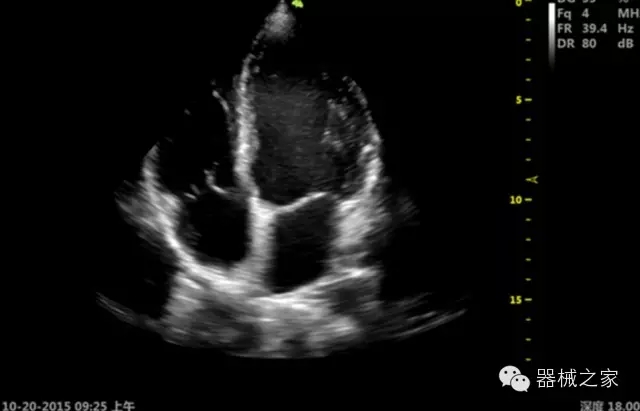

臨床圖片賞析

·心功能綜合指數(shù)(TEI指數(shù)):用于左、右心室整體心臟收縮舒張功能評(píng)估的測(cè)量方法;

·全方位可調(diào)M型:有利于更好的觀察心腔大小及室壁階段性運(yùn)動(dòng)的異常情況;

·組織多普勒成像(TDI):TDI可定量評(píng)價(jià)心肌運(yùn)動(dòng),判斷是否有局部病變,還可評(píng)價(jià)早期的舒張功能;